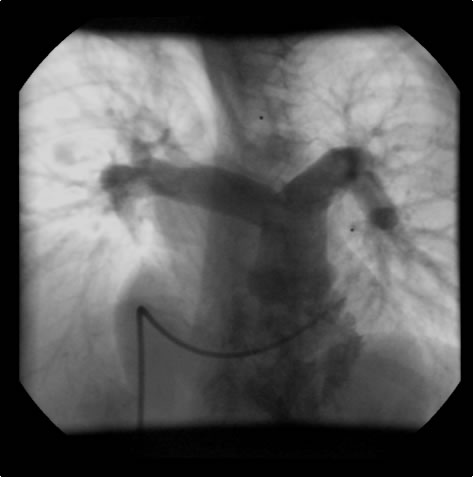

An asymptomatic, 5-year-old, 18-kg boy known by genetic testing to have Williams syndrome on physical examination had a IV/VI harsh systolic ejection murmur and no diastolic murmur. Preoperative echocardiogram showed an aortic root dimension of 2 cm and the dimension at the level of stenosis in the ascending aorta was 8 mm. Peak echocardiogram gradient was 70 mm Hg with a cardiac catheterization gradient of 50 mm Hg. The child had no peripheral pulmonary artery stenosis.

Preoperative transesophageal echocardiogram in long-axis view shows ascending aorta with aortic valve to the left. The markers indicate the aoritc root dimension to be 2.0 cm and hte mid portion of the stenosis to be 0.8 cm.